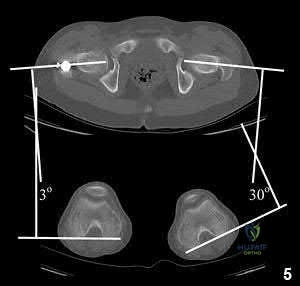

A 37-year-old male sustained the injury shown in figure A. He was treated with an intramedurally nail and a post-operative radiograph is shown in figure B. He underwent a post-operative CT Scanogram to assess for rotation. Figures C and D are of the operative side and Figures E and F are of the uninjured side. What is the version of the injured side and should any further procedures be undertaken for correction?

Jaarsma et al. detail how to obtain a rotational profile of the femur. Rotational alignment is determined by the angle between a line tangential to the femoral condyles and a line drawn through the axis of the femoral neck. The difference in angle between the fractured and unaffected side determines the rotational alignment. A decrease in anteversion of the femoral neck of the fractured side implies increased external rotation and an increase denotes increased internal rotation of the distal fragment.

Figure A demonstrates a subtrochanteric femur fracture, while Figure B demonstrates the same fracture, stabilized with a piriformis entry nail. Figures C-F demonstrate axial CT cuts to determine femoral version. Figure C demonstrates hip anteversion of 18 degrees, while figure D reveals knee external rotation of 18 degrees. This side exhibits neutral rotation (18-18).

Figure E demonstrates hip anteversion of 9.2 degrees while figure F demonstrates knee external rotation of 3.2 degrees. This side exhibits 6 degrees of anteversion (9.2-3.2).

Illustration A shows a CT evaluation of femoral malrotation. The angle on the uninjured side measures 30°, while the malrotated fractured side measures only 3°, indicating a 27° external rotation deformity.

Illustration A shows the typical CT scanogram cuts used to measure femoral version. Note, femoral version is obtained by measuring an angle between a line along the femoral neck and another line along the posterior condylar axis.